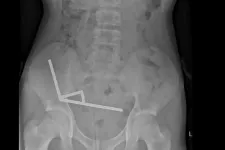

Száz darab erős mágnest rendelt a Temuról, hogy lenyelhesse őket, meg kellett műteni a 13 éves...

A mágnesek egymáshoz tapadtak odabenn, négy napig bírta a hasi görcsöket a fiatal.